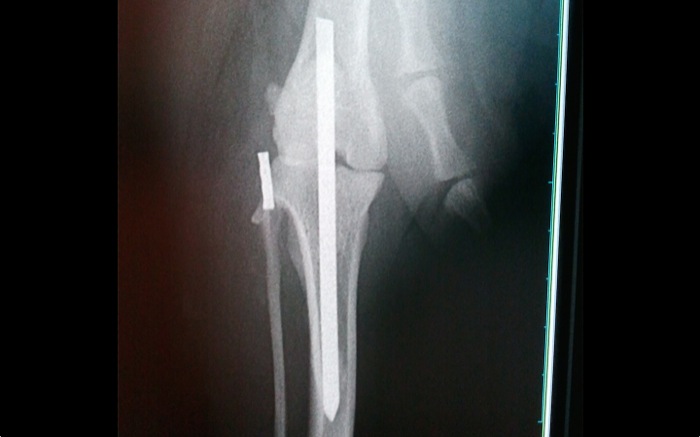

Una vez limpia la articulación de coágulos, fibrina, restos de ambos ligamentos cruzados y meniscos se implanta un clavo centrado y encima del surco rotuliano. El lugar de salida es exactamente en el origen del ligamento cruzado craneal para entrar posteriormente en la meseta tibial donde este ligamento debiera insertarse.

La artrodesis o anclaje articular temporal queda en la posición esperada en un segundo intento. Se realizó previamente una prueba con una aguja de Kirshner de pequeño calibre pero la dirección de salida no era idónea. Sí en un nuevo intento saliendo distal y por el centro de la cresta tibial.

El control habitual intraquirúrgico donde normalmente se valoran estabilidades, grados de movilidad, roces o no de los implantes, tensiones, etc. no es posible en este caso y es por ello que se tiene aún mas cuidado en conseguir una posición concreta de los implantes. No obstante recordemos que la inmovilidad articular impedirá cualquier lesión o roce en zonas de inserción del clavo.